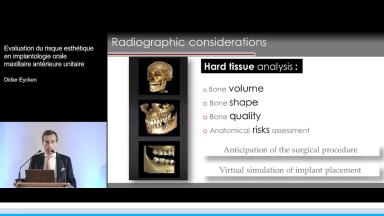

La présentation s’attache à détailler en quoi l’implantation en zone esthétique constitue un challenge lorsqu’il s’agit de réhabiliter la fonction sans oublier de rétablir l’esthétique. A travers quelques cas cliniques, le Dr Eycken s’appuie sur la classification SAC de l’ITI pour évaluer la complexité du cas et y apporter la solution thérapeutique adaptée. Il revient également sur l’importance du positionnement de l’implant dans les 3 sens de l’espace et sur la qualité des tissus mous environnants.

- de cerner les situations cliniques à risque dans le cadre de la pose d’un implant au maxillaire antérieur

- de positionner un implant correctement dans les 3 plans de l’espace